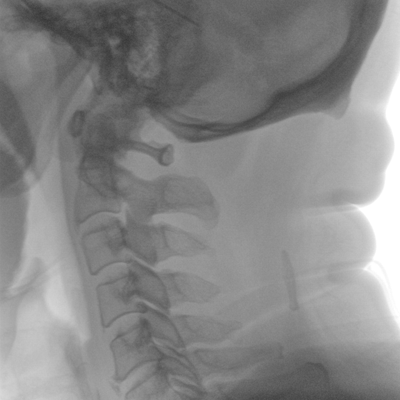

大尺寸液晶顯示器,圖像顯示清晰細(xì)膩;顯示器可大角度旋轉(zhuǎn),滿足臨床多角度觀察圖像的需要。